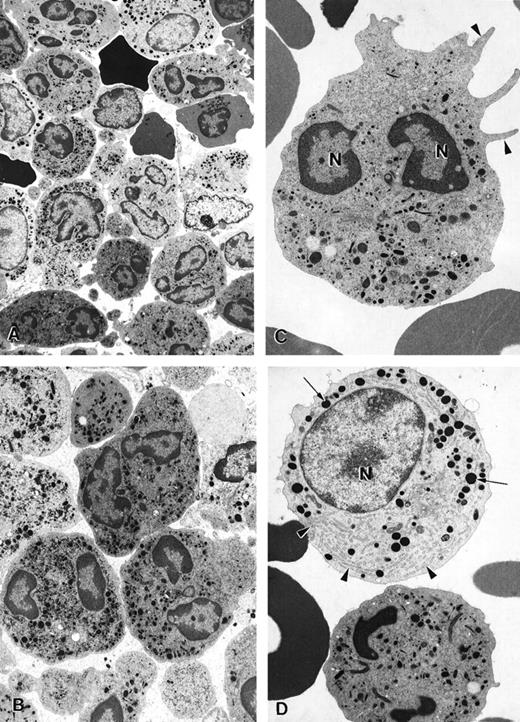

Electron microscopy of bone marrow cells in myelokathexis

The ultrastructure of bone marrow cells from patient 2 and a healthy volunteer donor was investigated before and during G-CSF therapy using electron microscopy (Figure 4). The bone marrow aspirate from a healthy volunteer contained predominantly neutrophils at various stages of maturation and immature red blood cells (Figure 4A; arrowheads). Few degenerating cells and minimal cellular debris were observed. In contrast, numerous degenerating cells (indicated by arrows) were present in the bone marrow aspirate from a patient with myelokathexis. In the degenerating cells, typical features of apoptosis were present, including the convoluted nucleus in an otherwise still intact cell. The granules (G) were aggregated, and the heterochromatin was concentrated in distinct, dense granular patches located on the inner surface of the nuclear membrane (Figure 4B). At higher magnification, apoptotic features such as cytoplasmic blebbing (arrowheads) and intense condensation of chromatin in the nucleus (N) were readily apparent in neutrophils (Figure 4). Macrophages were observed with numerous phagosomes that contained cellular debris as a result of phagocytizing senescent cells (Figure 4D). These apoptotic features were not present in the bone marrow aspirate from a healthy volunteer. These data indicated that accelerated apoptosis occurs in vivo in the myeloid precursor population in patients with myelokathexis.

Electron micrographs of bone marrow from patient 2 before granulocyte colony-stimulating factor treatment.

(A) Low magnification of the bone marrow shows degenerating cells (*), few mature neutrophils (**), and promyelocytes (arrows). Neutrophils with convoluted nuclei (arrowheads), a sign of early apoptosis, are observed. Magnification ×4000. (B) Macrophage in the bone marrow contains several phagosomes (arrows) with cellular debris of neutrophils. Neutrophil (arrowheads) with a distinguishable nucleus (*) and granules is discernible in 1 of the phagosomes. N, macrophage nucleus. Magnification ×6500. (C) Neutrophil in an early stage of apoptosis. The nucleus is convoluted (arrowheads), and the chromatin is condensed and distinctly circumscribed, forming dense granular masses (*) along the inner surface of the nuclear envelope. Magnification ×7500. (D) Neutrophil in a later stage of apoptosis. The cell shows cytoplasmic blebbing (arrowheads) and cellular fragmentation (arrow). N, nucleus. Magnification ×13,000. (E) Promyelocytes observed in the bone marrow. The cell at the bottom left appears normal and has a large, round nucleus (N), numerous granules, and a well-developed rough endoplasmic reticulum (arrows). The cell at the top right is apoptotic, as indicated by the fragmented nucleus (*), and has distinct areas of condensed chromatin (arrowheads). Magnification ×5500.

Electron micrographs of bone marrow from patient 2 before granulocyte colony-stimulating factor treatment.

(A) Low magnification of the bone marrow shows degenerating cells (*), few mature neutrophils (**), and promyelocytes (arrows). Neutrophils with convoluted nuclei (arrowheads), a sign of early apoptosis, are observed. Magnification ×4000. (B) Macrophage in the bone marrow contains several phagosomes (arrows) with cellular debris of neutrophils. Neutrophil (arrowheads) with a distinguishable nucleus (*) and granules is discernible in 1 of the phagosomes. N, macrophage nucleus. Magnification ×6500. (C) Neutrophil in an early stage of apoptosis. The nucleus is convoluted (arrowheads), and the chromatin is condensed and distinctly circumscribed, forming dense granular masses (*) along the inner surface of the nuclear envelope. Magnification ×7500. (D) Neutrophil in a later stage of apoptosis. The cell shows cytoplasmic blebbing (arrowheads) and cellular fragmentation (arrow). N, nucleus. Magnification ×13,000. (E) Promyelocytes observed in the bone marrow. The cell at the bottom left appears normal and has a large, round nucleus (N), numerous granules, and a well-developed rough endoplasmic reticulum (arrows). The cell at the top right is apoptotic, as indicated by the fragmented nucleus (*), and has distinct areas of condensed chromatin (arrowheads). Magnification ×5500.

Effect of G-CSF treatment on survival characteristics of neutrophils and bone marrow-derived cell populations

Before G-CSF treatment, approximately 55% of peripheral blood neutrophils from patient 2 underwent spontaneous apoptosis during storage overnight in vitro. In contrast, only 10% apoptosis was observed in neutrophils from a healthy volunteer. During G-CSF treatment in vivo, the percentage of neutrophils from the patient with myelokathexis undergoing spontaneous apoptosis was substantially reduced. A similar effect of G-CSF treatment was observed for bone marrow cells in myelokathexis. During G-CSF treatment, the patient's bone marrow clearly contained fewer apoptotic neutrophils, as determined by electron microscopy (Figure7A). Round neutrophils, microvilli on the cell surface, and typically polymorphous nuclei were observed. Promyelocytes and an increased number of mature neutrophils were present, indicating the influence of G-CSF treatment (Figures 7B, 7C).

Electron micrographs of bone marrow cells from a myelokathexis patient 2 during granulocyte colony-stimulating factor treatment.

(A) Low-magnification image of bone marrow shows numerous differentiated neutrophils. Magnification ×3750. (B) Mature neutrophils in bone marrow observed at higher magnification appear normal and show negligible evidence of apoptosis. Magnification ×5000. (C) Mature neutrophil shows typical microvillar structures (arrowheads) on the cell surface. Nuclear lobes (N) appear normal and show regular chromatin distribution. Magnification ×7000. (D) Mature neutrophil (bottom) and promyelocyte (top) in the bone marrow. The promyelocyte contains extensive rough endoplasmic reticulum (arrowheads) and electron-dense granules (arrows). N, nucleus. Magnification ×7000.

Electron micrographs of bone marrow cells from a myelokathexis patient 2 during granulocyte colony-stimulating factor treatment.

(A) Low-magnification image of bone marrow shows numerous differentiated neutrophils. Magnification ×3750. (B) Mature neutrophils in bone marrow observed at higher magnification appear normal and show negligible evidence of apoptosis. Magnification ×5000. (C) Mature neutrophil shows typical microvillar structures (arrowheads) on the cell surface. Nuclear lobes (N) appear normal and show regular chromatin distribution. Magnification ×7000. (D) Mature neutrophil (bottom) and promyelocyte (top) in the bone marrow. The promyelocyte contains extensive rough endoplasmic reticulum (arrowheads) and electron-dense granules (arrows). N, nucleus. Magnification ×7000.

To investigate the cellular and molecular defects responsible for ineffective granulocytopenia in myelokathexis, we studied 4 patients from 2 unrelated families. The morphologic appearance of bone marrow-derived cells from these patients, as determined by light and electron microscopy, demonstrated that mature marrow and blood neutrophils, as well as myeloid-committed precursors, underwent degenerative changes that were characterized by profound apoptotic features, including extended cytoplasmic membrane blebbing, granule aggregation, cytoplasmic vacuolization, and intensive condensation of heterochromatin in the nucleus (Figure 4). Such apoptotic cells became hypofunctional and were removed from the intramedullary space by bone marrow macrophages through phagocytosis (Figure 4).